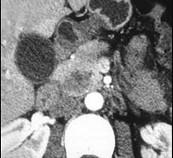

问题 女,56岁,腹部胀痛不适、食欲减退,影像表现如下图,最佳诊断是 ( )

选项 A.急性胰腺炎 B.慢性胰腺炎 C.胰腺腺癌 D.胰腺转移癌 E.胰腺假性囊肿

答案 C